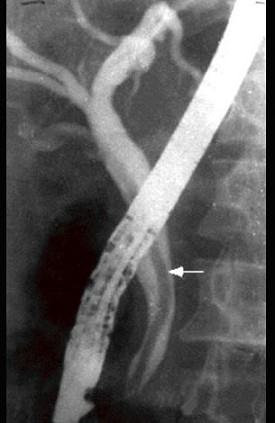

选项 A、阑尾炎的压痛、反跳痛主要在右下腹 B、胆道蛔虫病常出现腹膜刺激征 C、胃、十二指肠溃疡穿孔的压痛、反跳痛以上腹部最明显 D、胰腺炎病人血尿淀粉酶增高 E、胆总管结石的腹痛常伴发热和黄疸